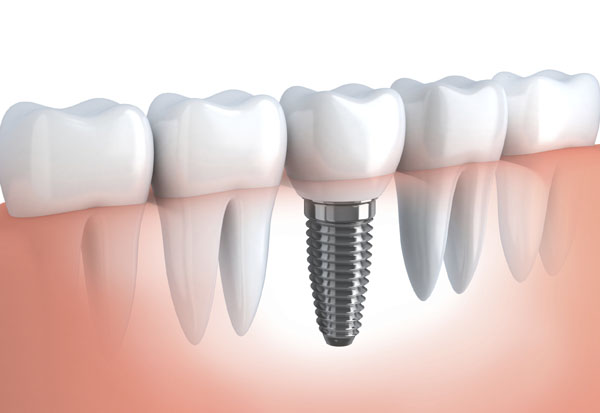

POPULAR DENTAL PROCEDURES